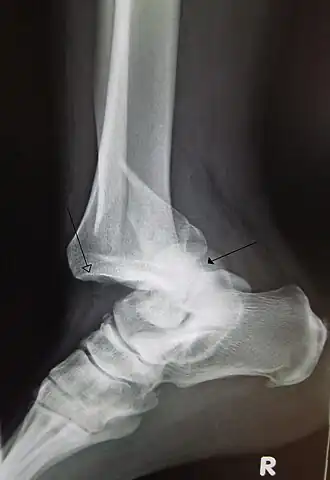

Dislocación traumática del tobillo con fractura del peroné distal. La flecha izquierda marca la ubicación de la tibia y la flecha derecha indica el astrágalo. | ||